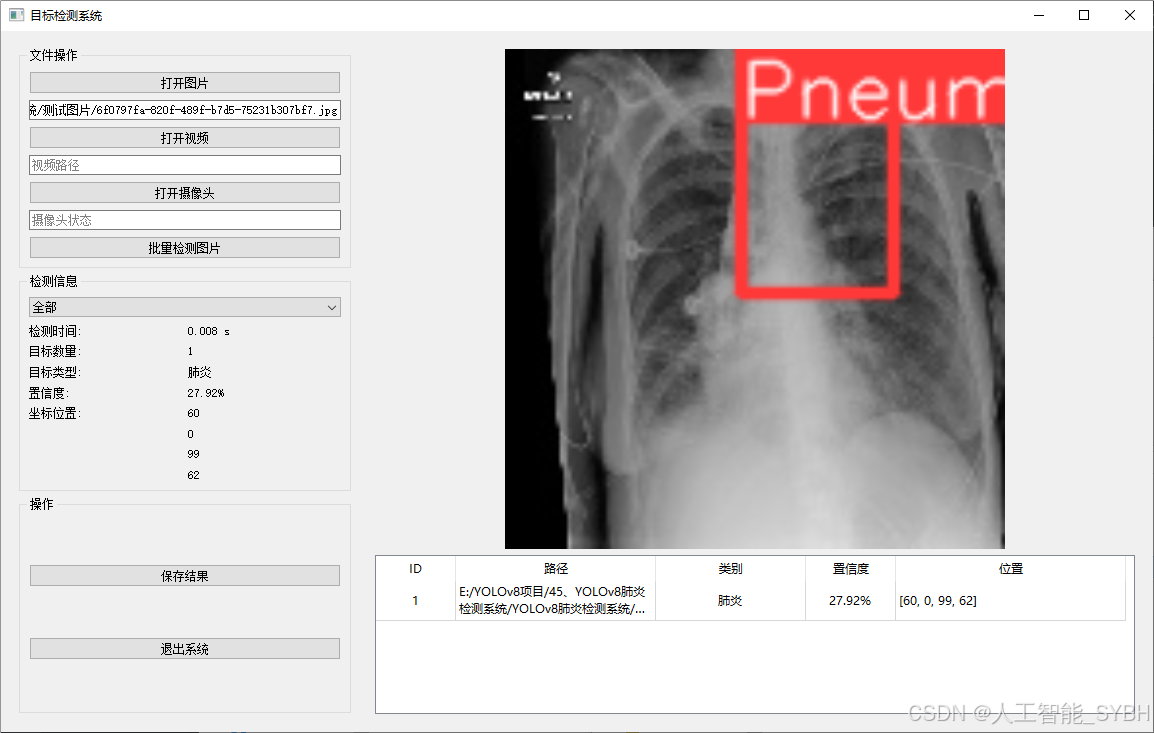

二、项目功能展示

系统功能

✅ 图片检测:可对单张图片进行检测,返回检测框及类别信息。

图片检测

该功能允许用户通过单张图片进行目标检测。输入一张图片后,YOLO模型会实时分析图像,识别出其中的目标,并在图像中框出检测到的目标,输出带有目标框的图像。批量图片检测